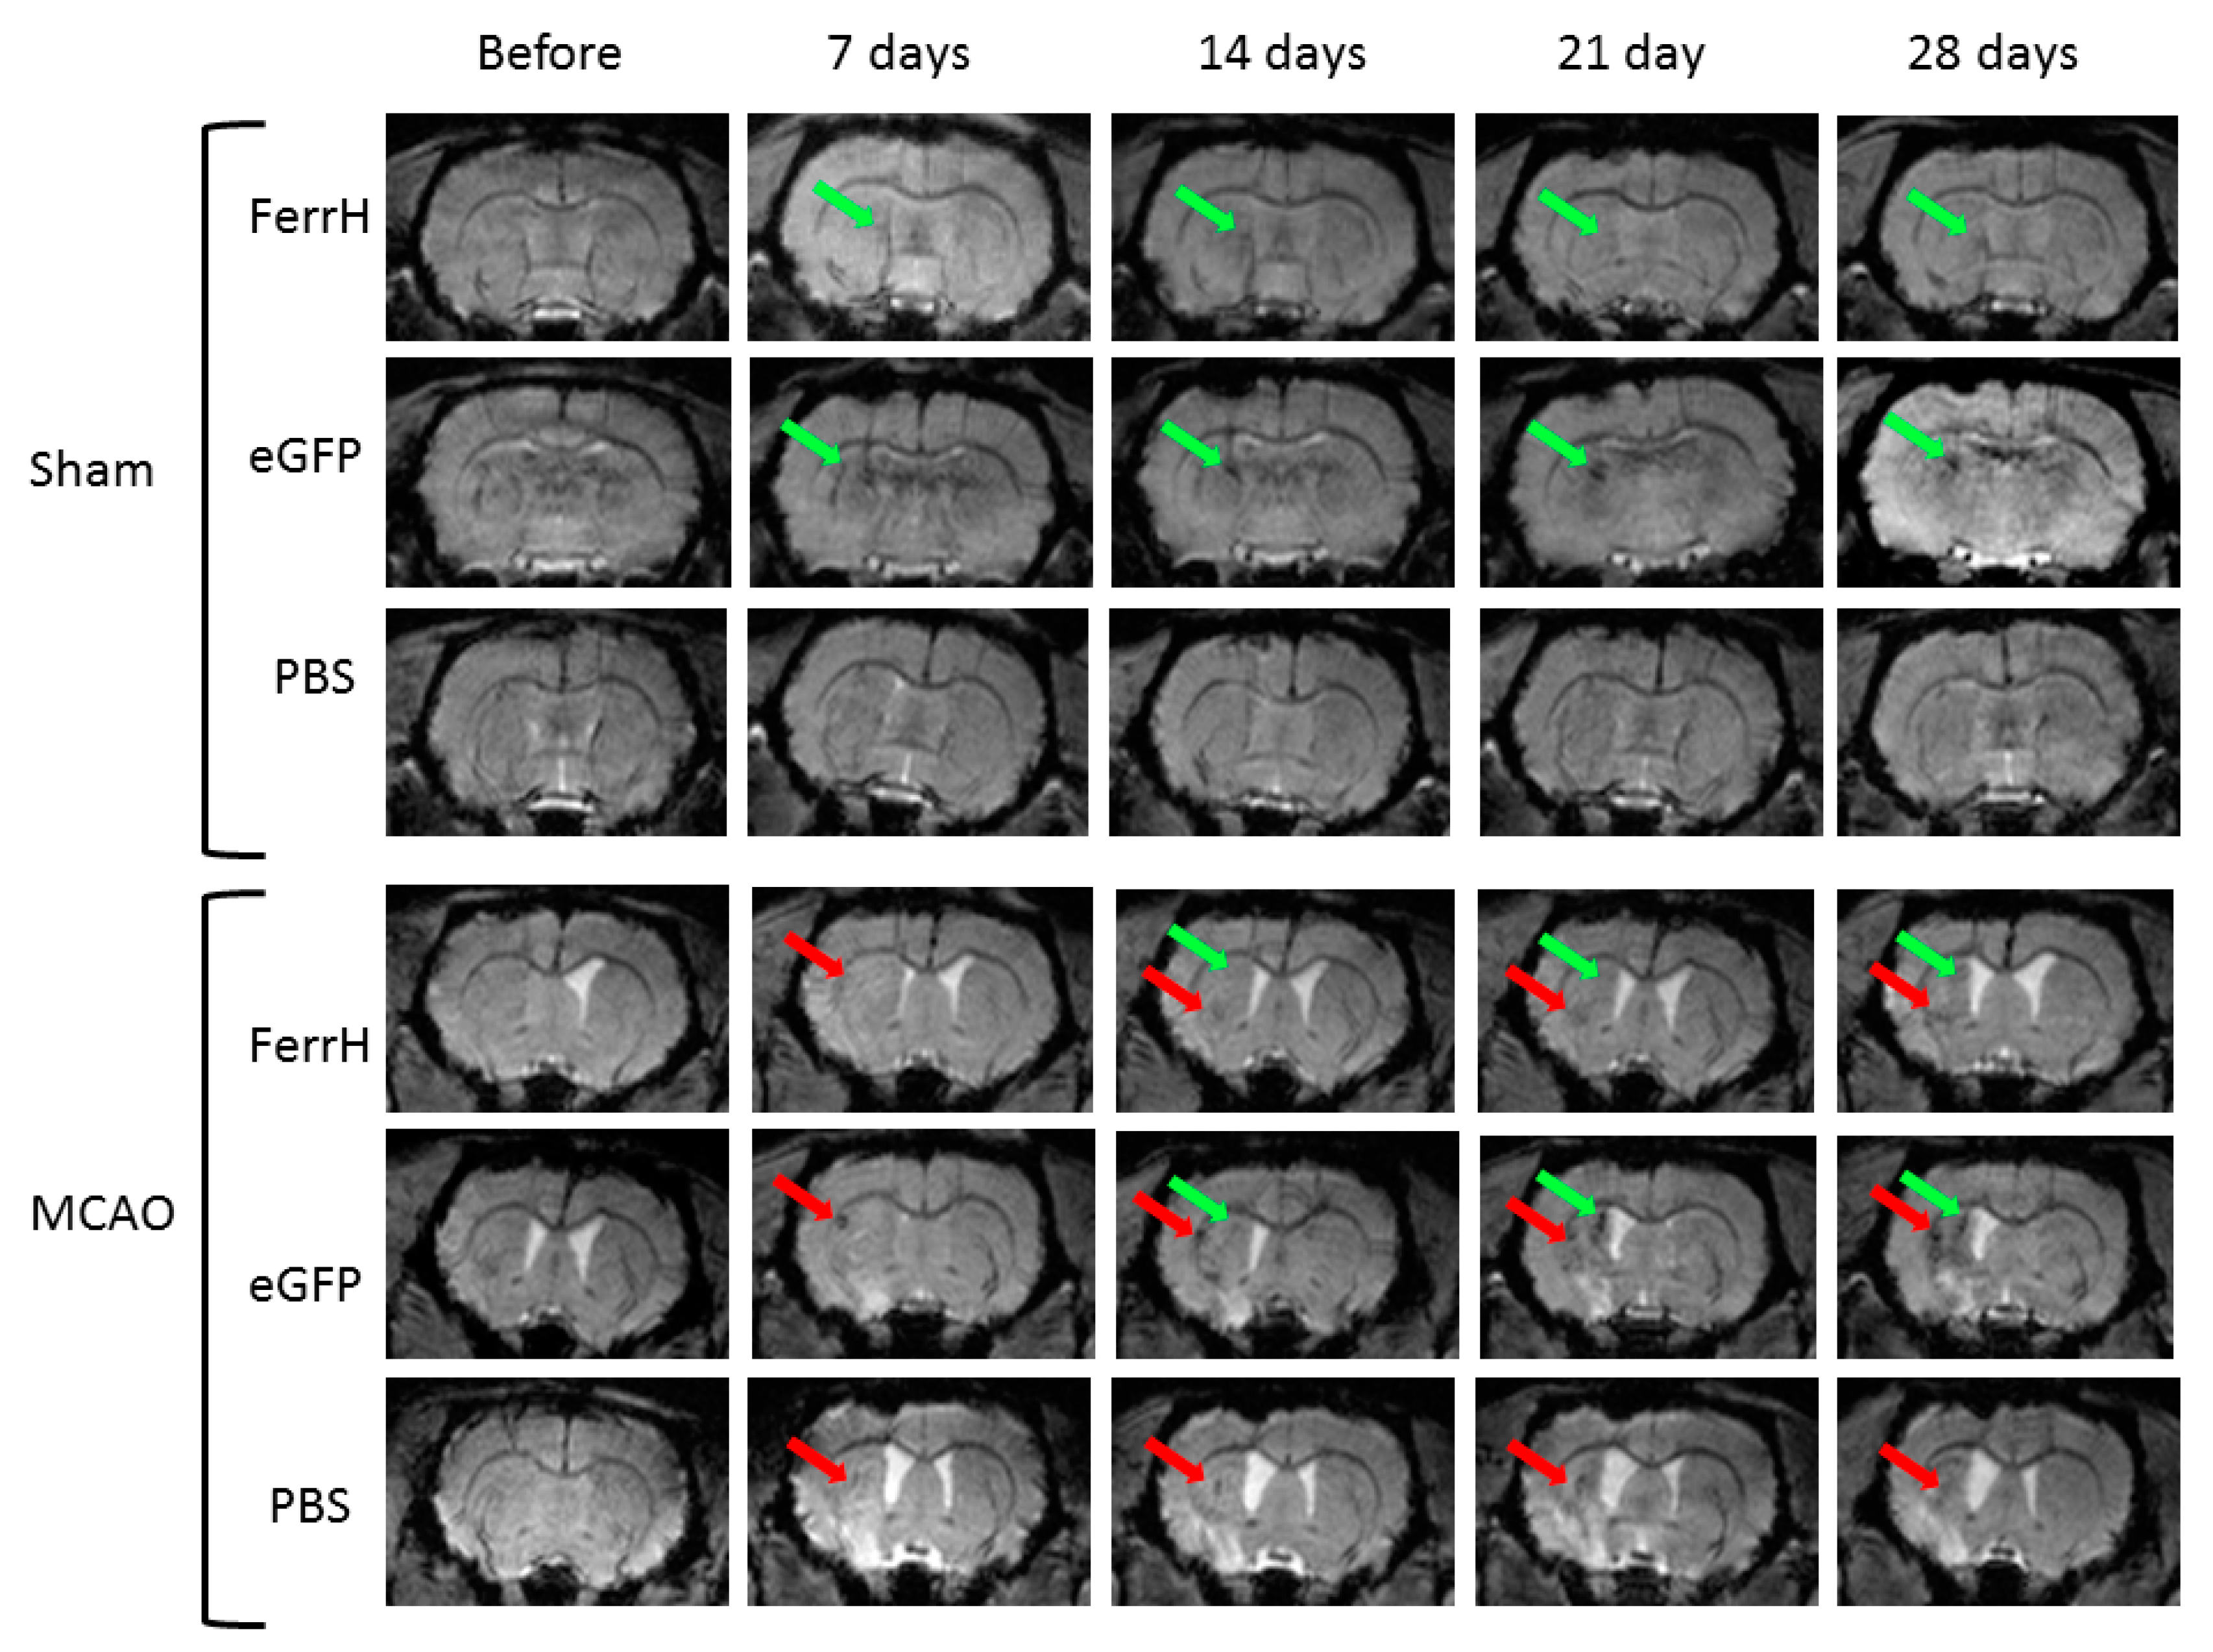

2.2. Injections of Both AAV-pDCX-FerrH and AAV-pDCX-eGFP Cause Signal Hypointensity on T2*-MGE Images in the Sham-Operated and Post-Ischemic Animals

- Results of our study showed that rat brain could be successfully infected with AAV-pDCX-FerrH and AAV-pDCX-eGFP viral vectors for expression of either ferritin or eGFP. Both vectors caused at about 20% decrease in signal hypointensity in the areas near the SVZ on T2*-weighted MRI at one month after intracranial injection of the viral constructs.